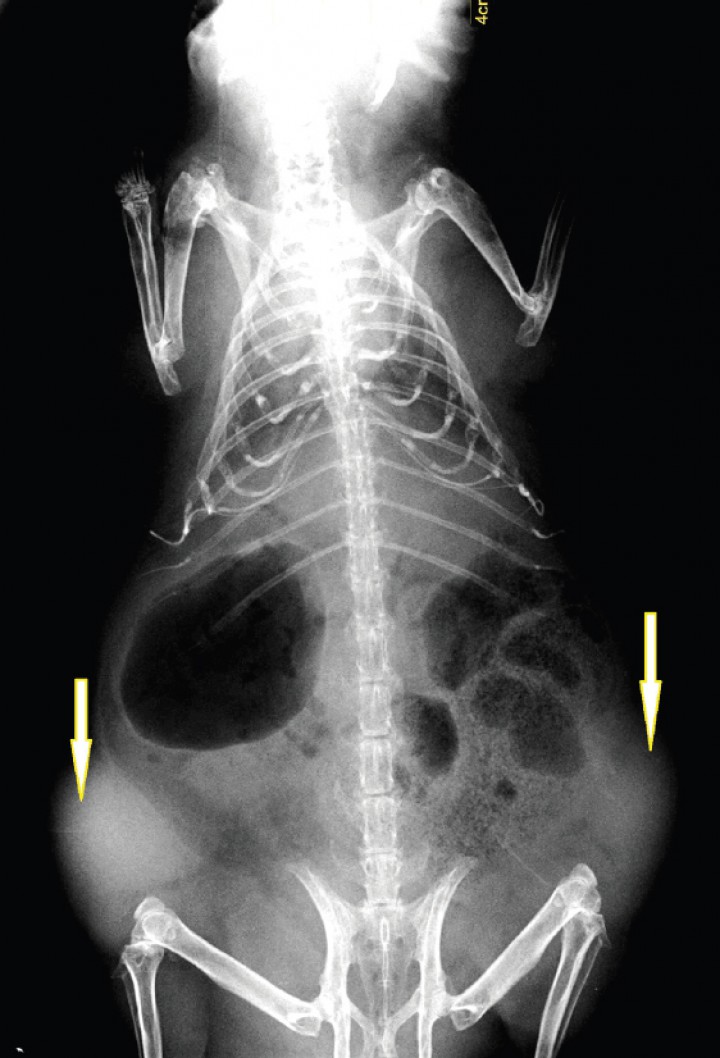

Durante la exploración física se evidencia una alopecia bilateral en los flancos, sin eritema ni descamación (Fig. 5). Tampoco hay cambios de coloración de la piel, pero se detecta la presencia de dos masas palpables a ambos lados del abdomen caudal, de consistencia bastante sólida. Se decide realizar una exploración ecográfica en la que se evidencian dos masas de ecogenicidad mixta, sin presencia de líquido, descartando además, por la situación anatómica, que se trate de quistes ováricos. Se sospecha que las masas son extraabdominales y se realiza una radiografía donde se constata que ambas son subcutáneas, quedando confirmado que no sean quistes o tumores de origen ovárico (Fig. 6).

Figura 6

Proyección ventrodorsal del caso nº 2. Se observan dos masas de opacidad tejido blando (flechas) localizadas en el subcutáneo.